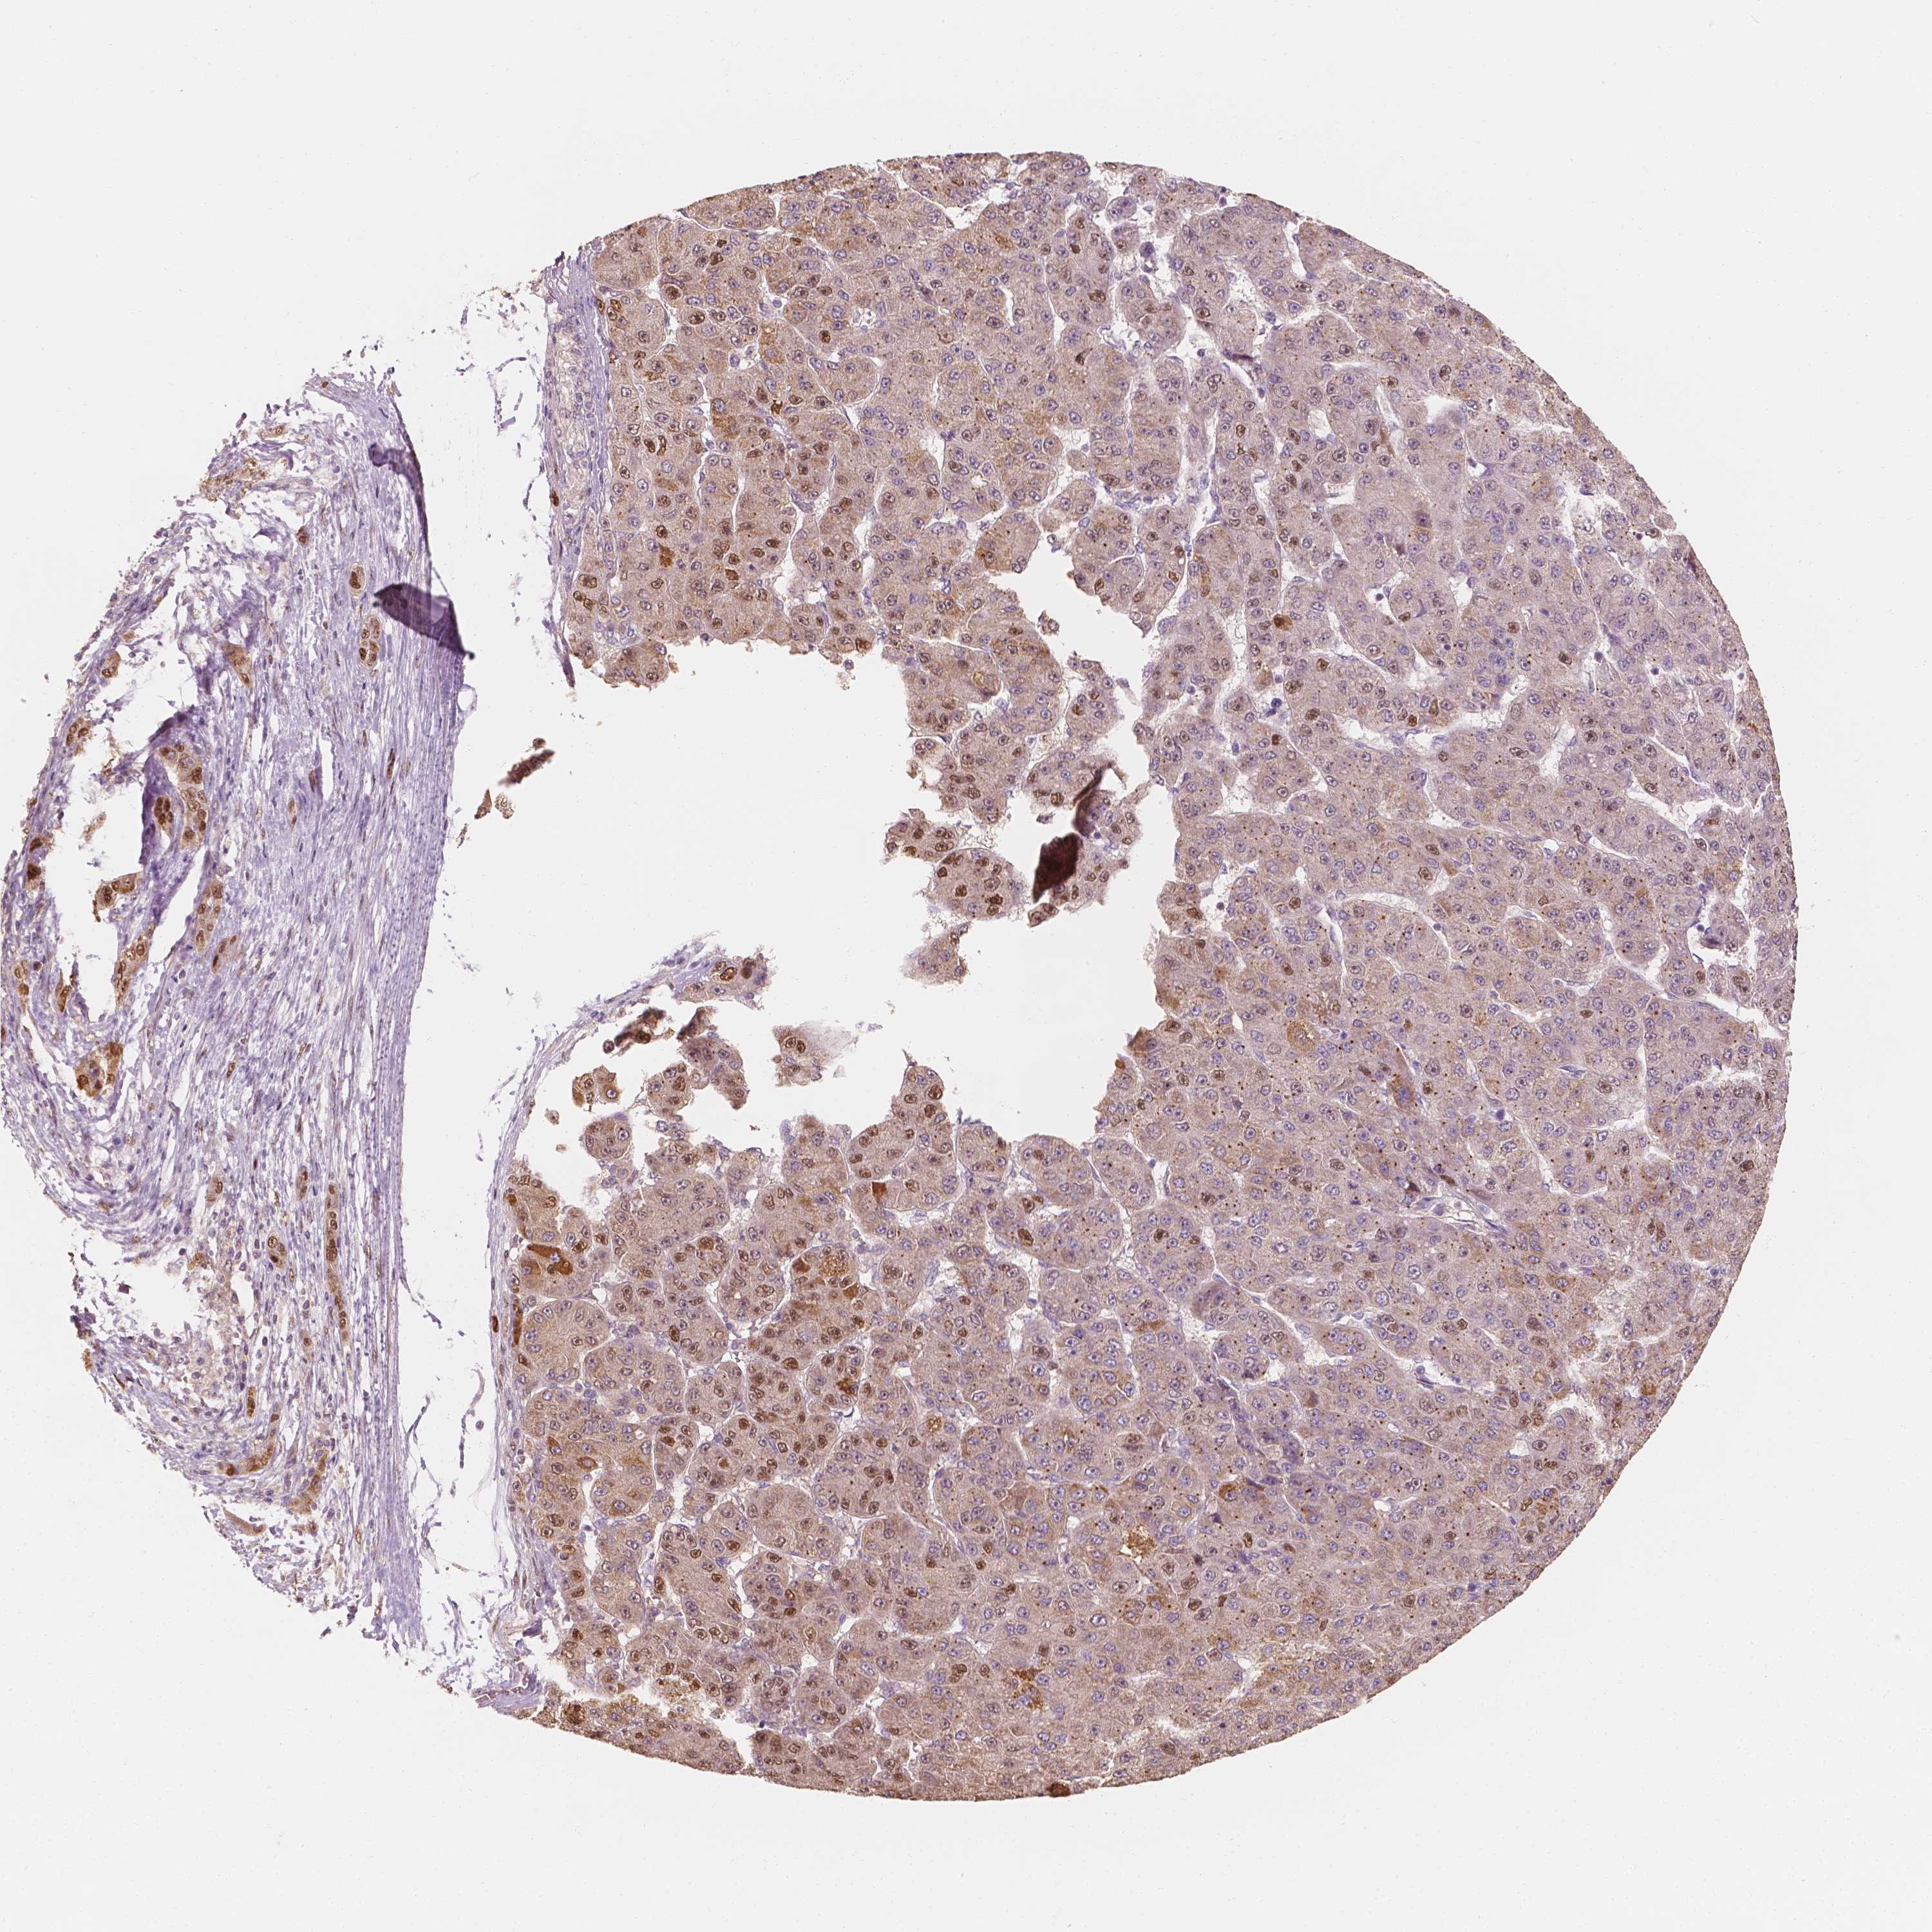

LIVER CANCER - Protein expressioni

A mouse-over function shows sample information and annotation data. Click on an image to view it in a full screen mode. Samples can be filtered based on level of antibody staining by selecting one or several of the following categories: high, medium, low and not detected. The assay and annotation is described here.

Note that samples used for immunohistochemistry by the Human Protein Atlas do not correspond to samples in the TCGA dataset.

Antibody stainingi

Antibody staining in the annotated cell types in the current human tissue is reported as not detected, low, medium, or high, based on conventional immunohistochemistry profiling in selected tissues. This score is based on the combination of the staining intensity and fraction of stained cells.

Each image is clickable and will lead to virtual microscopy that enables deeper exploration of all samples and also displays staining intensity scores, fraction scores and subcellular localization as well as patient and tissue information for each sample.

Antibody HPA068119

Staining

High

Medium

Low

Not detected

Intensity

Strong

Moderate

Weak

Negative

Quantity

>75%

75%-25%

<25%

None

Location

Nuclear

Cytoplasmic/membranous

Cytoplasmic/membranous,nuclear

Carcinoma, Hepatocellular, NOS

Cholangiocarcinoma